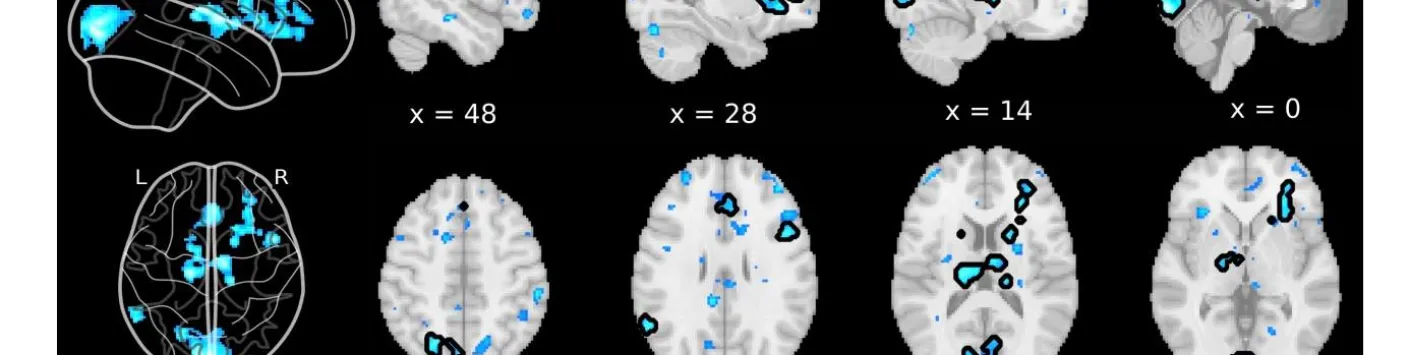

Les désactivations du cerveau entier précèdent les rapports de suppression de l'esprit non induits

➡ Ici, les auteurs de cette étude, dont notamment Paradeisios Alexandros Boulakis, Aspirant FNRS Université de Liège, Sepehr Mortaheb Aspirant FNRS Université de Liège, Steve Majerus, Promoteur PDR FNRS Université de Liège et Athena Demertzi, Chercheuse qualifiée FNRS Université de Liège visent à examiner cette hypothèse en déterminant les corrélats neuronaux de la MB sans induction.